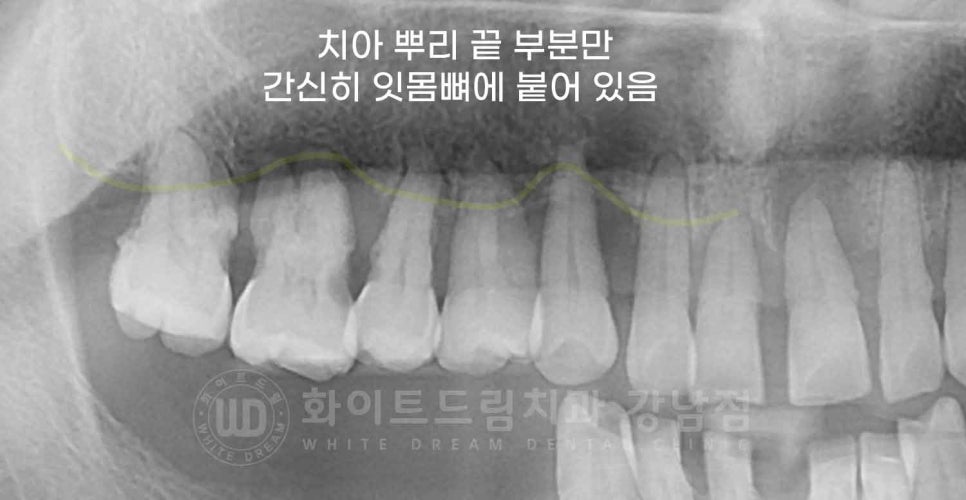

▲ 환자분의 초진 x-ray. 치주염이 심해 치아 뿌리만 간신히 잇몸뼈에 붙어 있습니다.

잇몸뼈가 녹아 잇몸뼈의 높이가 점점 낮아지면 치아를 잡고 있던 잇몸뼈가 사라지면서 치아가 흔들리기 시작하는 것이죠.

그러다 치아가 더 이상 버티지 못하면 치아가 하나둘씩 빠지게 되는데요.